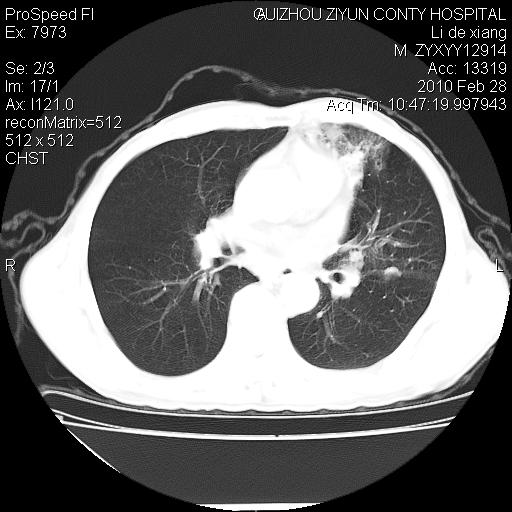

标题: CT24776:男 71Y 咳嗽咳痰胸痛两月,伴声音嘶哑。 [打印本页]

左侧中央型肺癌伴左肺上叶阻塞性肺炎及节段性不张可能性大,建议纤支镜检查!

左侧中央型肺癌伴左肺上叶阻塞性肺炎及节段性不张可能性大,建议纤支镜检查!纵隔淋巴结转移.

左肺门部肿块,伴左上肺斑块影,周边模糊,支持左肺中央型肺癌伴节段性不张及阻塞性肺炎,结合支气管镜检查。

左上叶支气管狭窄,阻塞性病变,肺门肿块,纵隔及肺门淋巴结增大,中央性肺癌